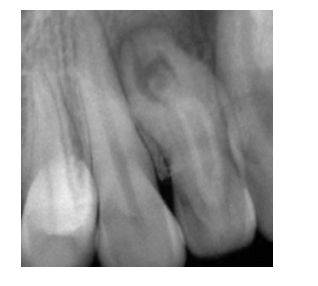

**Dentinogenesis Imperfecta**

Failure in Bell Stage Autosomal Dominant * intrinsic alteration of dentin * affects all teeth (primary and permanent) * short roots, bell-shaped crowns, **obliterated pulps** * **Bulbous Crowns** in radiographs due to constricted DEJ * **Blue Sclera** (also linked to osteogenesis imperfecta) * tx: Full coverage crowns for esthetics